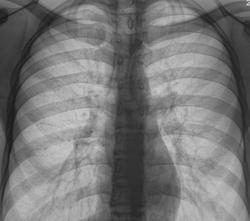

Прошло 3 месяца, и сегодня, фтизиатр прислал на «контроль», взятого на заметку.

Стало ясно, что линейная томография в данном случае не повредит.

Какое мнение будет после томографии у уважаемых коллег?

Формально фтизиатры поставят диагноз инфильтративный туберкулез S6 правого легкого, фаза распада. Но, я не зря спросил про возраст больного. У молодых людей нижнедолевой туберкулез особенно в 6 сегменте часто связан с поражением внутригрудных лимфатических узлов. Пути распространения инфекции лимфобронхогенное. Подтверждением этого является обнаружение при бронхоскопии различных форм активного туберкулеза (инфильтративный, язвенный и лимфобронхиальный свищ). При бронхоскопии у больного могут найдут специфическое поржение бронхов. Лимфогенный путь распространения напоминает раковый лимфангиит . О лимфогенном распространении инфекции указывает прединфильтратная сетка, которую хорошо видно на рентгенограммах. О поражении лимфатических бронхопульмональных узлов свидетельствует вовлечение в процесс плевральных листков в виде воспалительного уплотнения междолевой плевры, а также наклонность к раннему образованию распада. Известно,что у взрослых трудно выявить изменения со стороны ВГЛУ, так как они не часто достигают той величины, как у детей. Умеренно выраженное увеличение бронхопульмональных л/у на КТ диагностируется только при контрастировании. Таким образом, предварительный патогенетический диагноз звучал бы так : туберкулез внутригрудных лимфатических узлов бронхопульмональной группы справа, осложненный бронхолегочным поражением в S6 с распадом. Необходимо построить патогенетический диагноз, так как специфические изменения в лимфатических узлах требуют более длительного лечения. Такова моя точка зрения на диагноз у представленного пациента. С уважением Ваш NIkolas